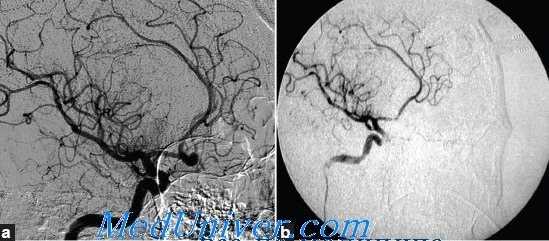

Семидесяти одному больному была выполнена 71 микрохирургическая операция: клипирование аневризмы проведено 58 больным; укрепление стенки аневризмы (окутывание фрагментом мышцы) – 4; клипирование, дополненное окутыванием аневризмы мышцей, выполнено 9 пациентам. Хороший результат (OGS 5–4) был достигнут у 81,7% больных. Неудовлетворительный и плохой результат (OGS 1-2) отмечен у 2,8% (рис. 3).

Рис. 3. Функциональный исход микрохирургических операций

При сравнении результатов хирургического лечения в зависимости от типа строения аневризмы было выявлено ухудшение результатов лечения после операций на фузиформных аневризмах. Частота благоприятных исходов (OGS IV-V) при фузиформном строении аневризмы была ниже (66,7%), чем при аневризмах других типов (80-84%). Различие достоверно (p<0,001).